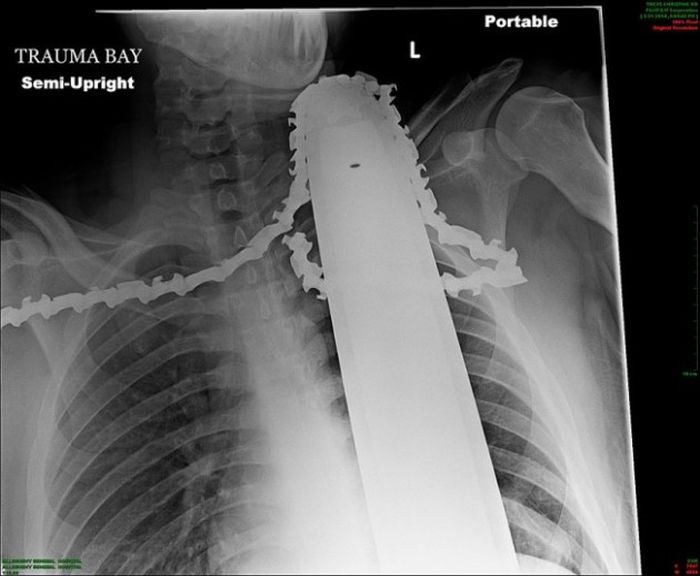

Жуткие рентгеновские снимки

Порой даже не верится, с какими странными и необычными повреждениями в травматологию могут поступить пострадавшие. Всю эпичность профессии врачей травматологии могут с легкостью подтвердить рентгеновские снимки. Просто жесть, да и только..